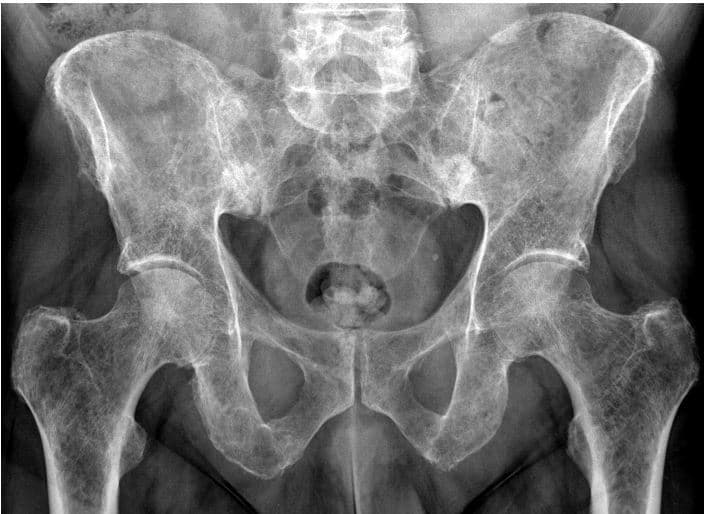

Are these bones axial, appendicular, or both?

How would you describe the fracture?

Name the type of fracture

List ALL the bones present

What may have caused this abnormality?

Describe the fracture

Determine an approximate age range for this female patient. Explain why you chose that age.

Is this pelvis male or female? Explain